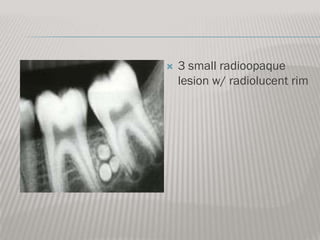

COMPOUND ODONTOMA RADIOGRAPHICLLY

*Most common odontogenic tumor

*Appears as a cluster of multiple abortive teeth

*Often prevents normal tooth eruption

*Radiographically multiple tiny toothlike structures

are contained within a fine radiolucent rim

*Do not recur after excision

*thus discovered during adolescence

   3 small radioopaque

lesion w/ radiolucent rim

COMPOUND ODONTOMA RADIOGRAPHICLLY *Most common odontogenic tumor *Appears as a cluster of multiple abortive teeth *Often prevents normal tooth eruption *Radiographically multiple tiny toothlike structures are contained within a fine radiolucent rim *Do not recur after excision *thus discovered during adolescence Histology of compound odontomas approaches normal tooth strcture. Gross clinical examination usually is sufficient for diagnosis.

3 small radioopaque lesion w/ radiolucent rim